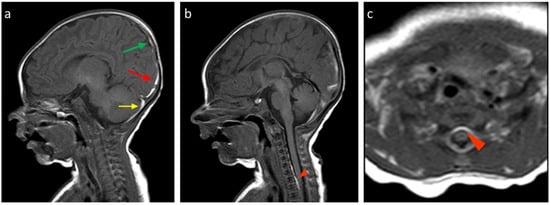

About the analysis of the SDH locations in the 32 patients which was the object of the study (Table 2, Table 3 and Table 4), the most common location was the cerebellum (31/32, 96.9%) followed by parietal and occipital lobes (19/32, 59.4%; 18/32, 56.2%, respectively), falx cerebri (11/32, 34.4%), tentorium cerebelli (10/32, 31.2%), temporal lobes (6/32, 18.7%), and finally, cervical and dorsal spine in the same patients (4/32, 12.5%, Figure 2, Figure 3, Figure 4 and Figure 5).

According to SDH locations, the patients were divided into supratentorial, infratentorial, both, and spinal canal (Table 5). Twenty-six patients (83%) showed simultaneous and/or bilateral co-involvement of multiple CNS areas. Cerebellum involvement occurred in almost all patients (31/32, 96.9%) except in one 3-day-old infant. In the cerebellum, bilateral involvement was observed in 78% (18/23) of males and 44.5% (4/9) of females. Parietal and occipital SDH were predominantly bilateral in both genders (68.7% and 100%, males and females, respectively), whereas tentorial hemorrhages were more frequently unilateral. The SDH of the falx cerebri and temporal area were more often bilateral in females, while males exhibited a higher prevalence of unilateral involvement in these areas.

The absence of hematomas with exclusive infratentorial localization is reported by Rooks et al. [], who also reveal that all their patients had a supratentorial involvement. On the other hand, a case with only supratentorial localization is described by Whitby et al. [], which describes six cases out of nine with exclusive infratentorial involvement. Rooks et al. [] also report 1/4 of newborns with a single site and 2/3 of cases with two or more localizations. In our study, the SDH predominant localization was infratentorial, compatible with the cerebellum localization (31/32, 96.9%) with a single un-affected case and with nine cases with exclusively infratentorial distribution, while no cases with only supratentorial localization were detected. In the latter localization, the most frequent distribution was the parietal one (19/32, 59.4%), followed by the occipital one (18/32, 56.2%), while SDH of the temporal lobe, tentorium cerebelli, and falx cerebri were rarer (6/32, 18.7%; 10/32, 31.2%; and 11/32, 34.4%, respectively). Our case series has highlighted a clear prevalence of male patients (23/32, 71.9%).

The most frequent localization was the cerebellum (31/32, 96.9%), with a single unaffected case, while no cases with only supratentorial localization were detected. The spinal canal represented the least involved site (4/32, 12.5%), with both cervical and dorsal involvement in the same patients. In particular, we observed very thin hematomas with anterior and/or posterior distribution. These cases were associated with a simultaneous involvement of both supratentorial and infratentorial CNS structures. After a month, these four spinal SDH patients were re-evaluated, and a complete resolution with restitutio ad integrum was reached.